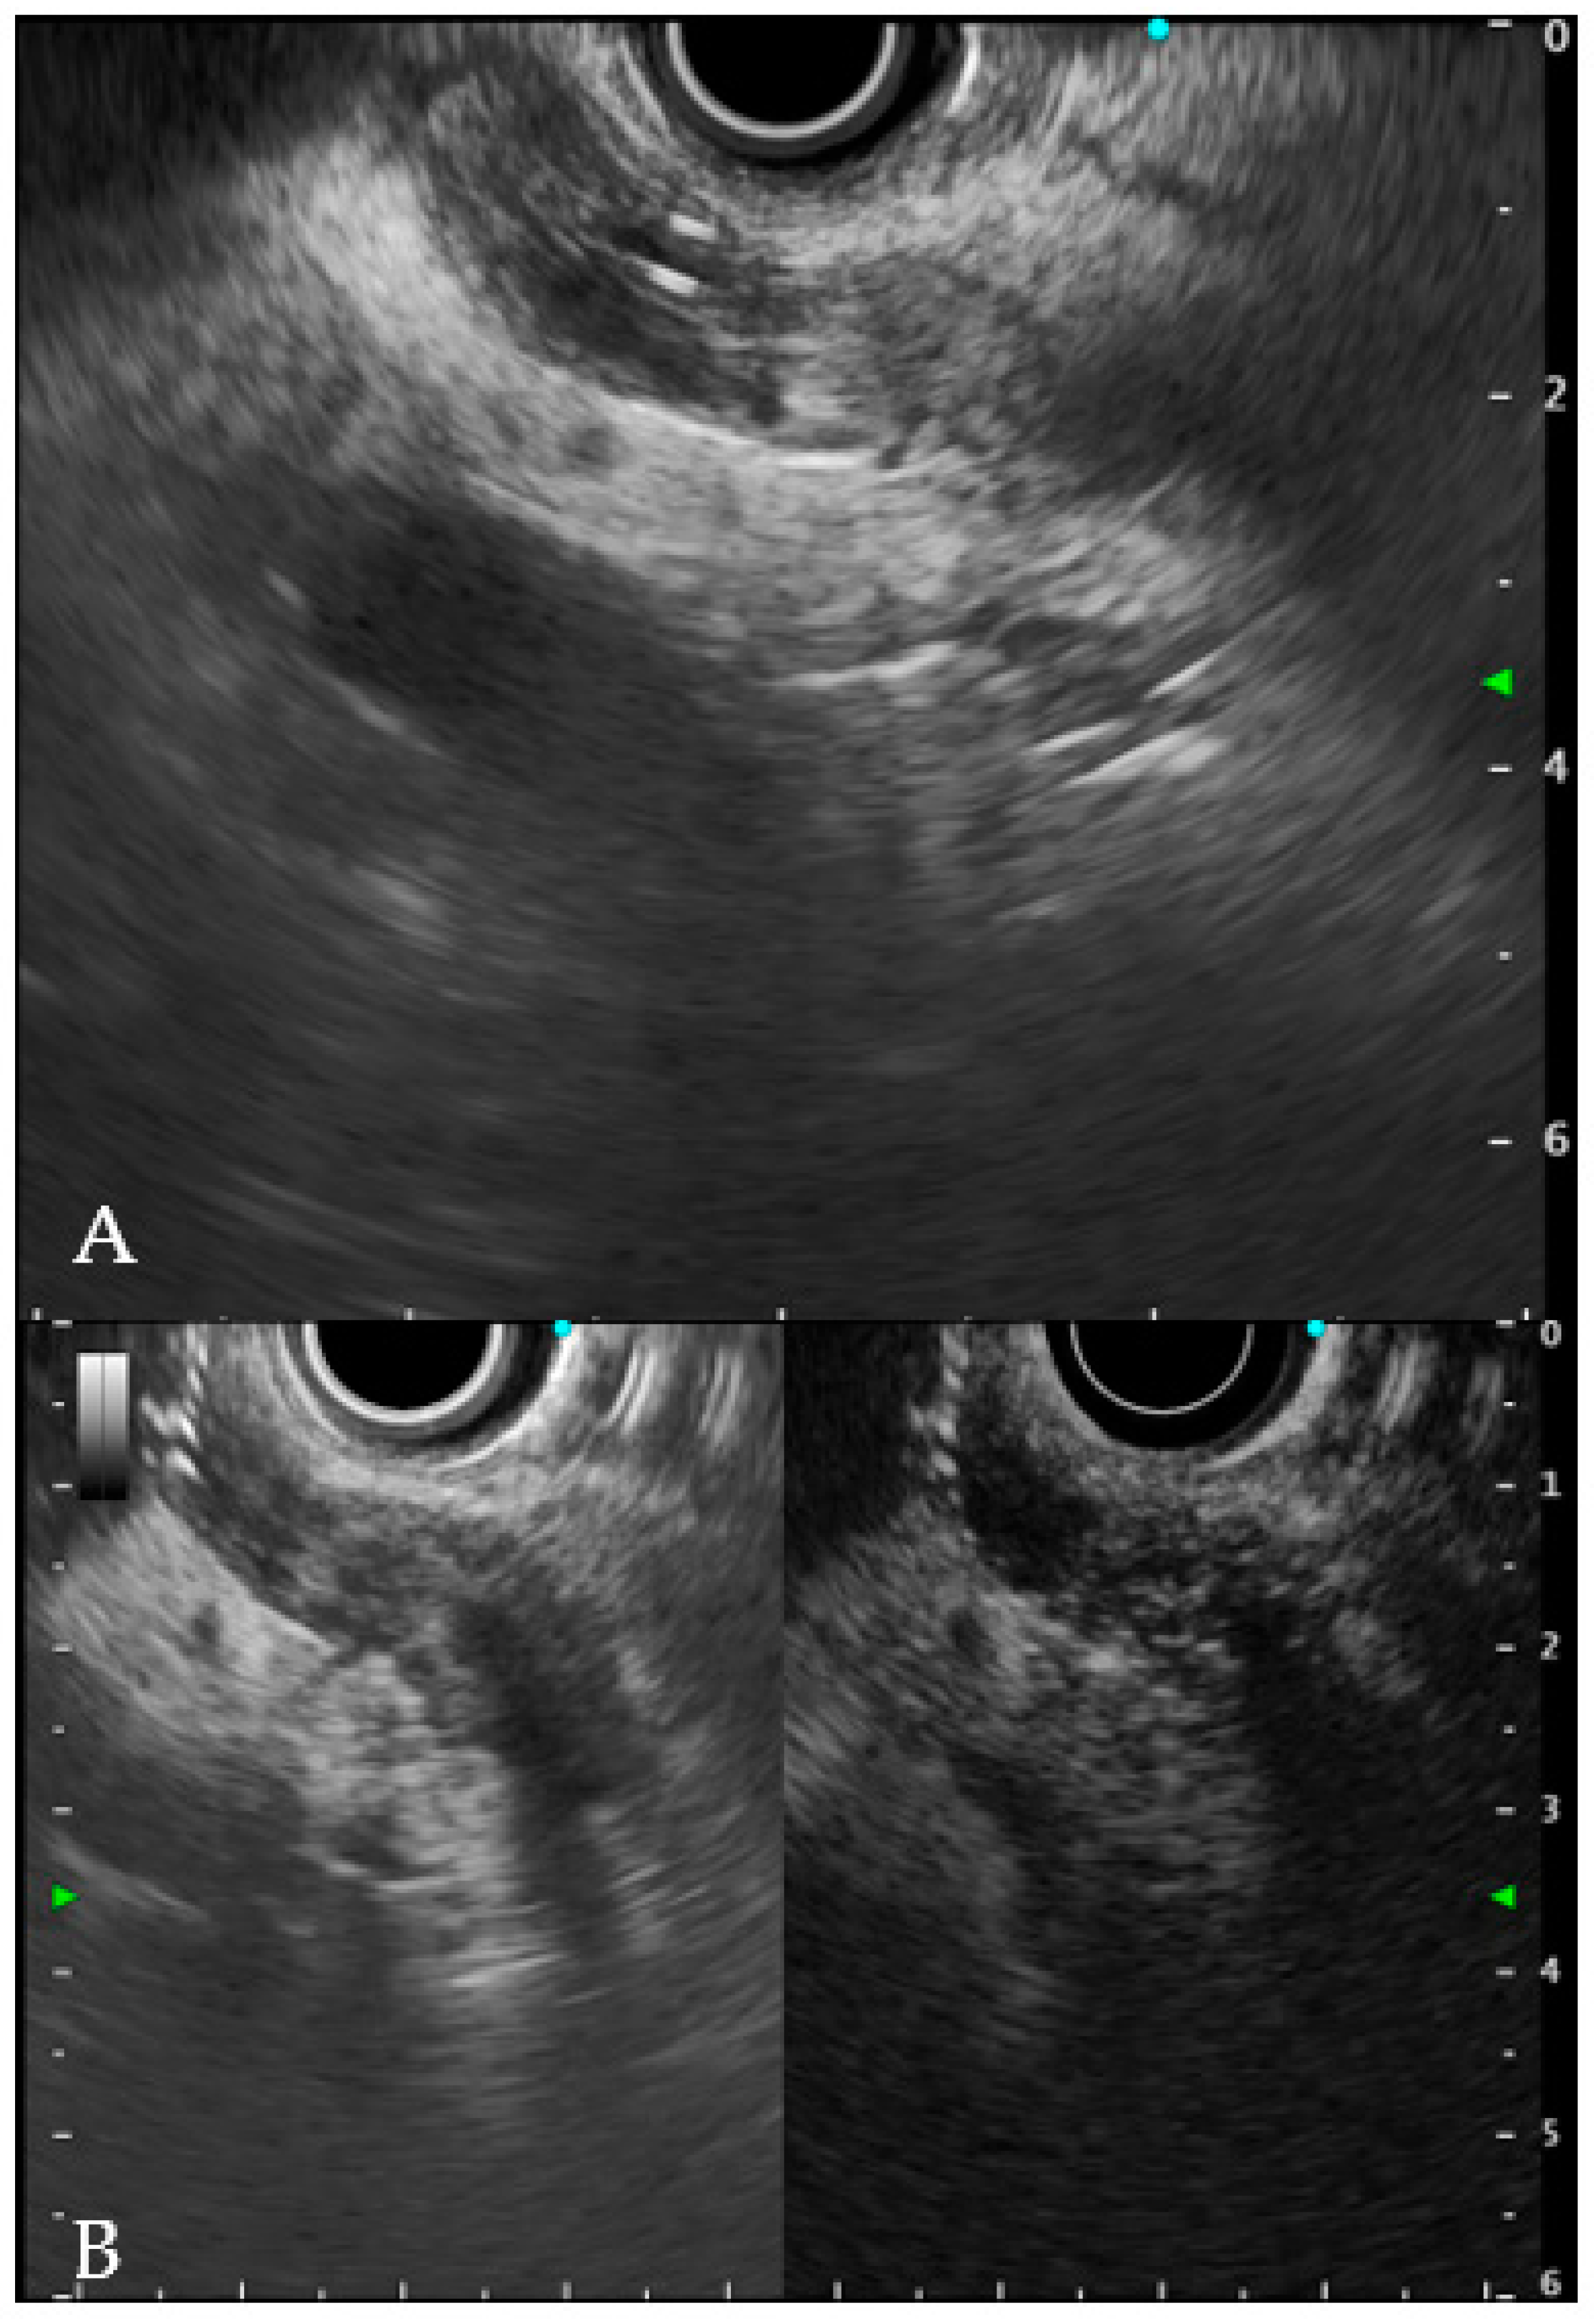

6.1. Intraductal Ultrasonography

6.2. Endoscopic Ultrasound